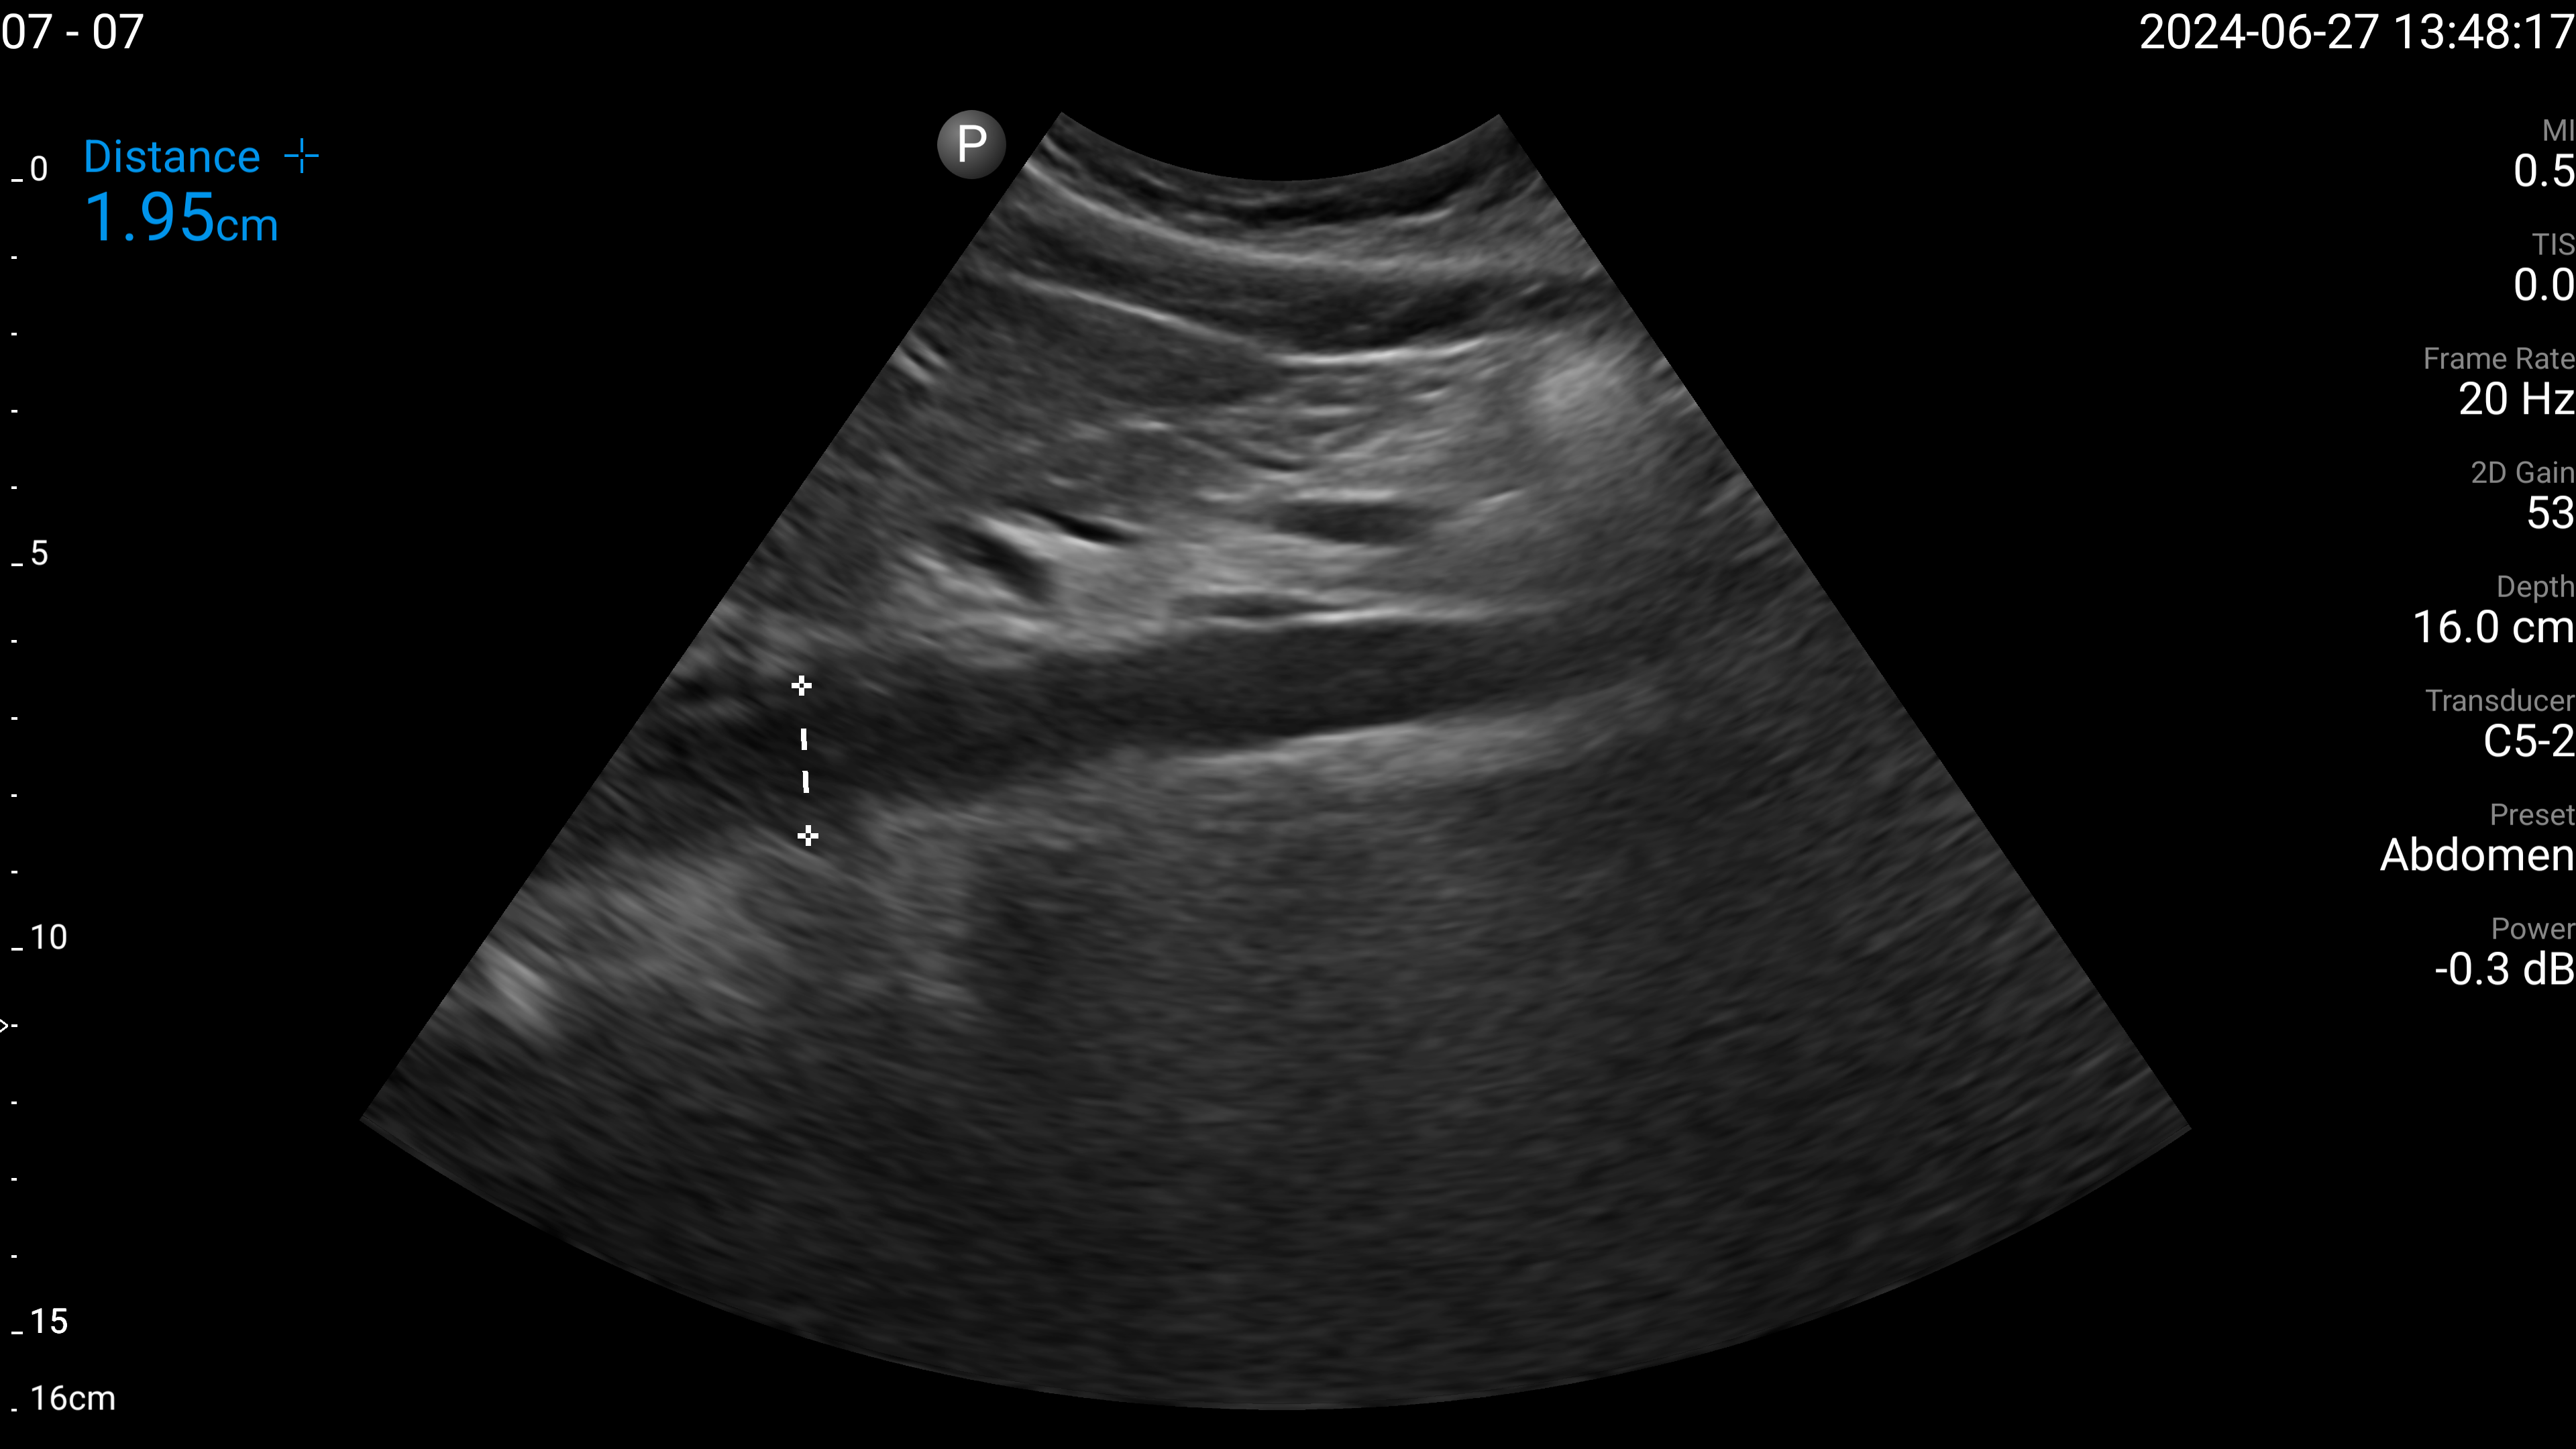

Refer to caption

(a) Proximal aorta with AP diameter.

(b) IVC - longitudinal.

(c) Left lobe of liver - long axis.

(d) Left lobe of liver - transverse.

(e) Right portal vein - transverse.

Figure 4: Examples of the target US images acquired by the sonographers using the human teleoperation system.

The sonographers completed 11 abdominal US scans, each with 5 target images and measurements for a total of 55 images. An example image of each of the targets acquired during these tests is shown in Fig. 4. After completing the scans, two radiologists scored the images based on quality, including identifying targets that could not be seen or were not captured (which were given a score of 0). The distribution of these scores is illustrated in Fig. 5. The first radiologist identified 4 out of the 55 targets as not visible, while the second radiologist identified 6 out of 55 as not visible. Combined, this accounted for 7 unique targets that at least one radiologist considered missing. Of these missing targets, three were not captured due to large amounts of bowel gas and body habitus while one was seen but the sonographer did not capture and save the image. When excluding all the missing targets, the images obtained a mean score of 4.28±0.95plus-or-minus4.280.954.28\pm 0.954.28 ± 0.95 out of 5 and 91.7% of the images were scored 3 or higher by both radiologists. A score of 3 or higher indicated the image quality was sufficient for basic image interpretation. 31.3% of the images were scored 5 by both radiologists, indicating the image quality was good and meaningful image interpretation was easy.